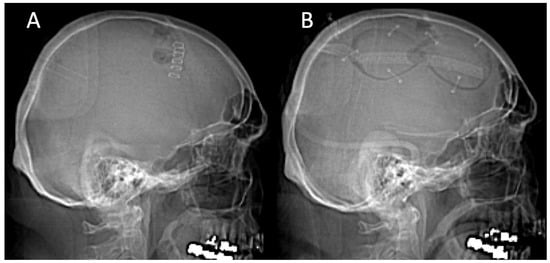

Unfortunately, 18 days after discharge, the patient developed a seizure disorder and showed right-sided hemiparesis and incomplete aphasia, resulting in a hospital readmission. The CT scan revealed progression of the left-sided cSDH with the flattening of the gyration and, thus, was seen as symptomatic (Figure 1A). A reexamination of the head CT revealed that a 71.8 mL cSDH had returned. The patient was taken to the operating room and underwent burr-hole trepanation and hematoma evacuation. However, due to the firm hematoma, no subdural drain placement was achievable, and the post-op CT scan revealed a postoperative subarachnoid hemorrhage (Figure 1B).

After the patient showed no clinical improvement, we identified an indication for revision surgery by means of craniotomy and hematoma evacuation, which was performed using the herein-introduced endless-loop craniotomy technique. Details of the surgical steps are displayed in the next section. Because of the vulnerable cortex and an already-present postoperative hemorrhage, we chose a non-watertight dura closure, and an epidural Jackson-Pratt drain was left for 2 days (Figure 1C,D). Figure 2 shows an illustration of the two different surgical techniques in a sagittal CT scout: burr-hole (A) and endless-loop craniotomy (B). The detailed operative steps for craniotomy, dura opening, and drain management are shown in Figure 3 and Figure 4. The operation was performed as planned without intraoperative complications.

Figure 1. (A,B): Pre- and post-burr-hole CT scans after left-sided cSDH evacuation in axial and coronal views. (C,D): Different window settings after revision surgery with endless-loop craniotomy and the placement of a Jackson-Pratt drain. The yellow horizontal line on the coronal slices shows the axial level.